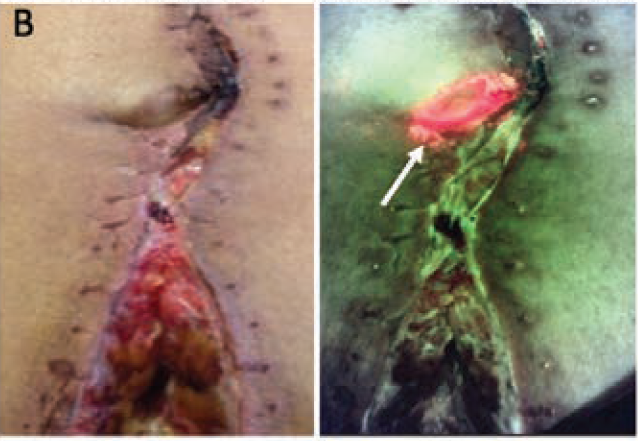

Multidisciplinary Strategies With Real-Time Fluorescence Images and Negative Pressure Wound Therapy to Manage Organ/Space Surgical Site Infection in Transplanted Kidneys

Chen, CH et al. Annals Plastic Surgery 2023